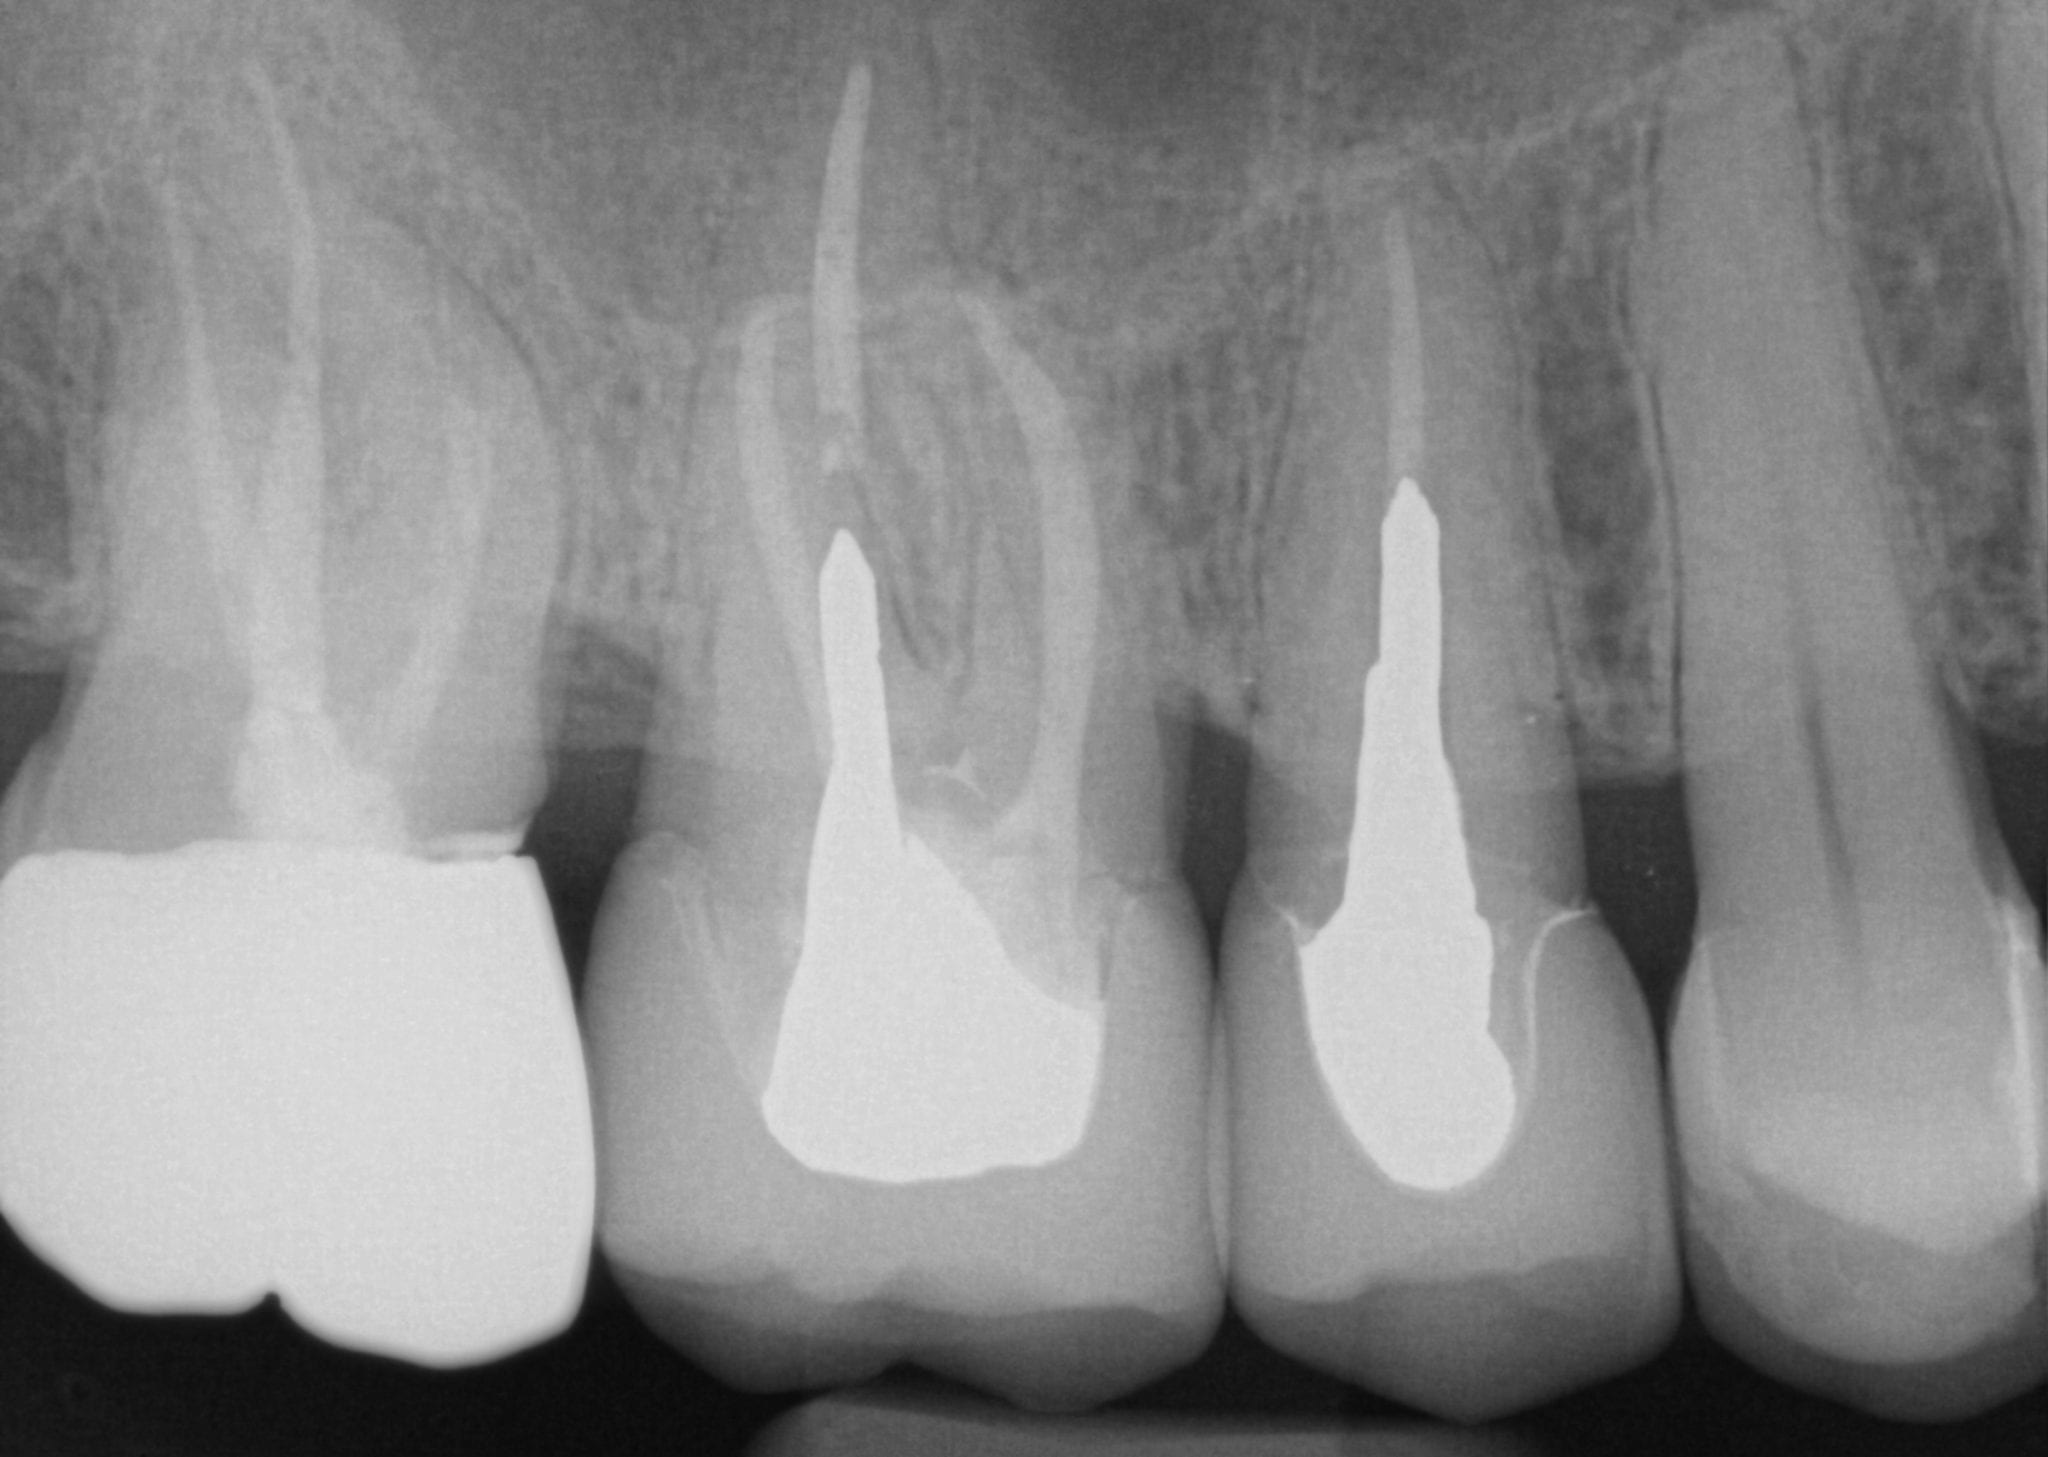

One Month Post Op with Radiographs